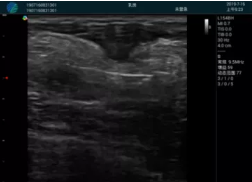

清晰顯示腺體內(nèi)低回聲快影,邊界清晰,包膜較光滑

確定進針路徑并實時監(jiān)測抽吸針與腫塊位置關系

抽吸針進入腫塊內(nèi)部進行旋切

抽吸過程中可見腫塊明顯縮小,并根據(jù)腫塊位置改變針道位置

抽吸旋切后再進行超聲復查,原腫塊區(qū)域未見殘留組織及出血